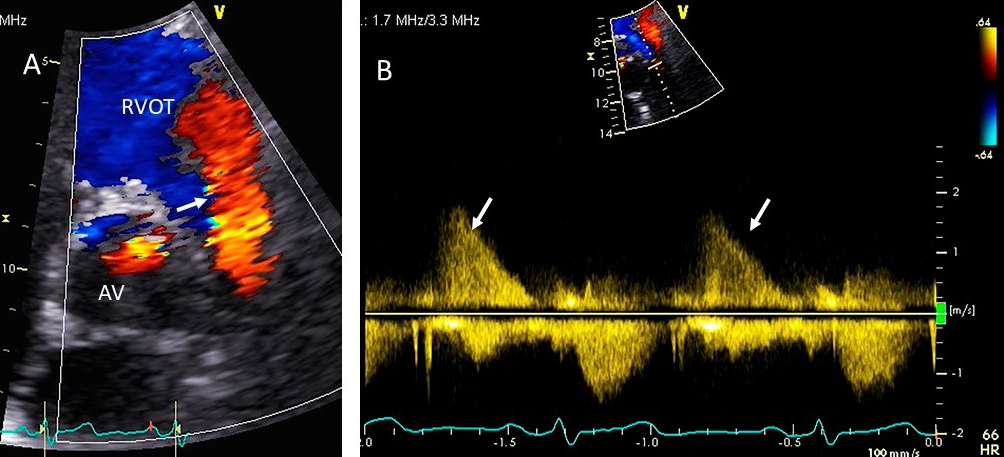

Significant pulmonary valve regurgitation (PR) in adults is generally seen in those with prior history of pulmonic valve surgery for congenital heart disease. PR can also result from significant pulmonary hypertension of any cause.

PR is diagnosed with color Doppler revealing diastolic flow in the RV outflow

tract (Fig. 11). In severe PR with normal PA pressures (e.g., primary PR), the

color jet has low velocity with laminar flow and the duration of the flow can be

misleading, as severe PR may lead to rapid equalization of the RV pressure with

diastolic pulmonary artery pressure, and thereby lead to a very short duration of

flow [67]. In secondary PR from pulmonary hypertension, the jet is aliased and

usually holodiastolic [68]. Severe PR from primary or secondary causes has an

intense spectral Doppler signal. Other parameters to assess PR severity include

PR jet width: if it occupies

Fig. 11.Pulmonic valve regurgitation. (A) TTE basal short axis view

showing color Doppler of pulmonic valve (in the long axis view) and aortic valve

in the short axis view. There is severe pulmonic regurgitation as shown by a wide

diastolic jet in the RVOT occupying